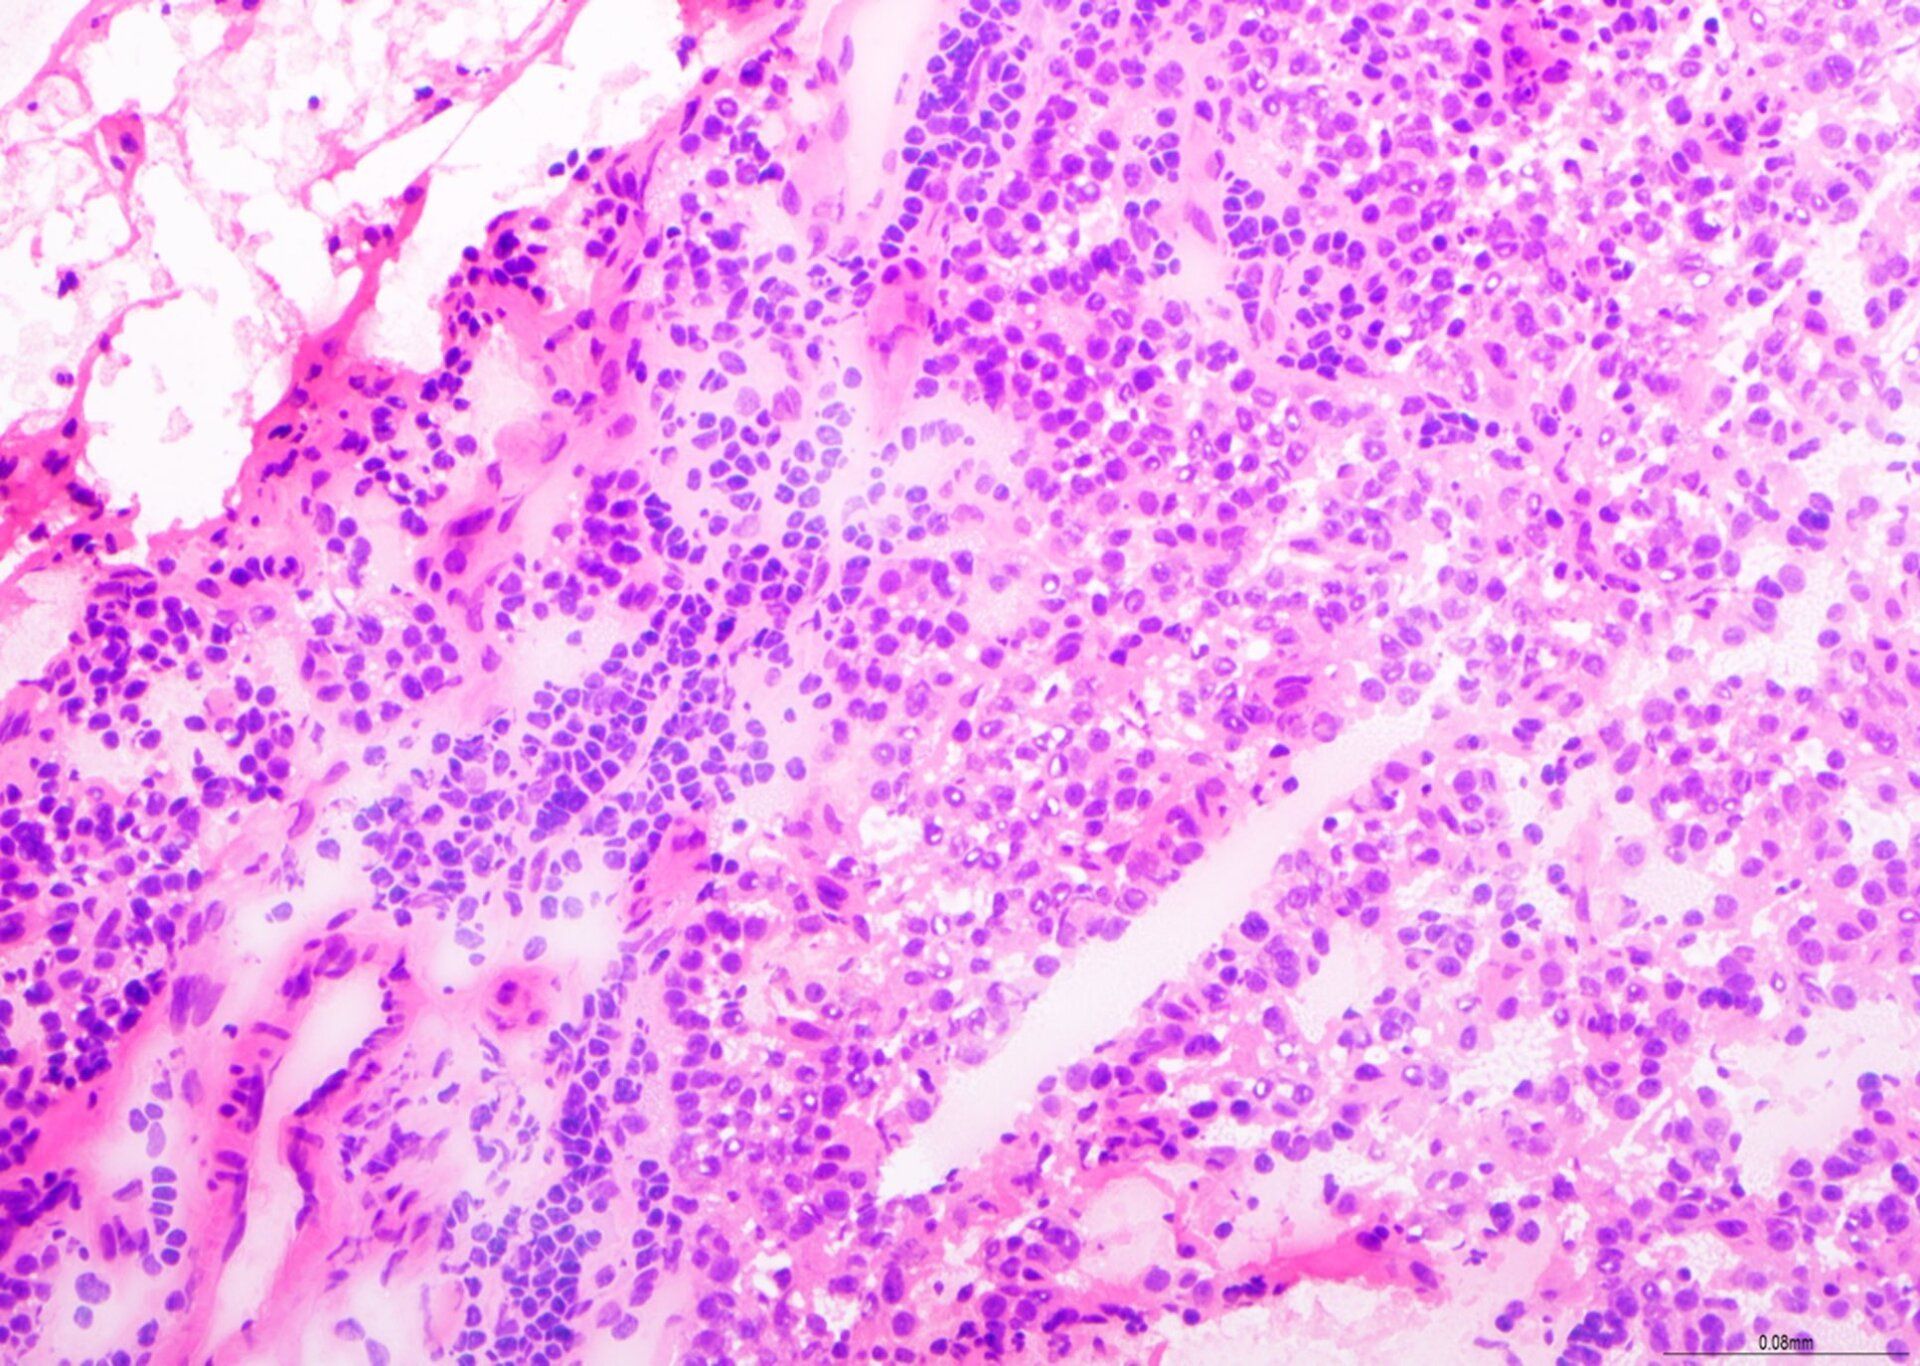

NADH - Muscle Scheme

Here’s an example of a slide from our Muscle Scheme showing the NADH method. This image shows excellent fibre type demonstration and scored 10/10 at assessment!